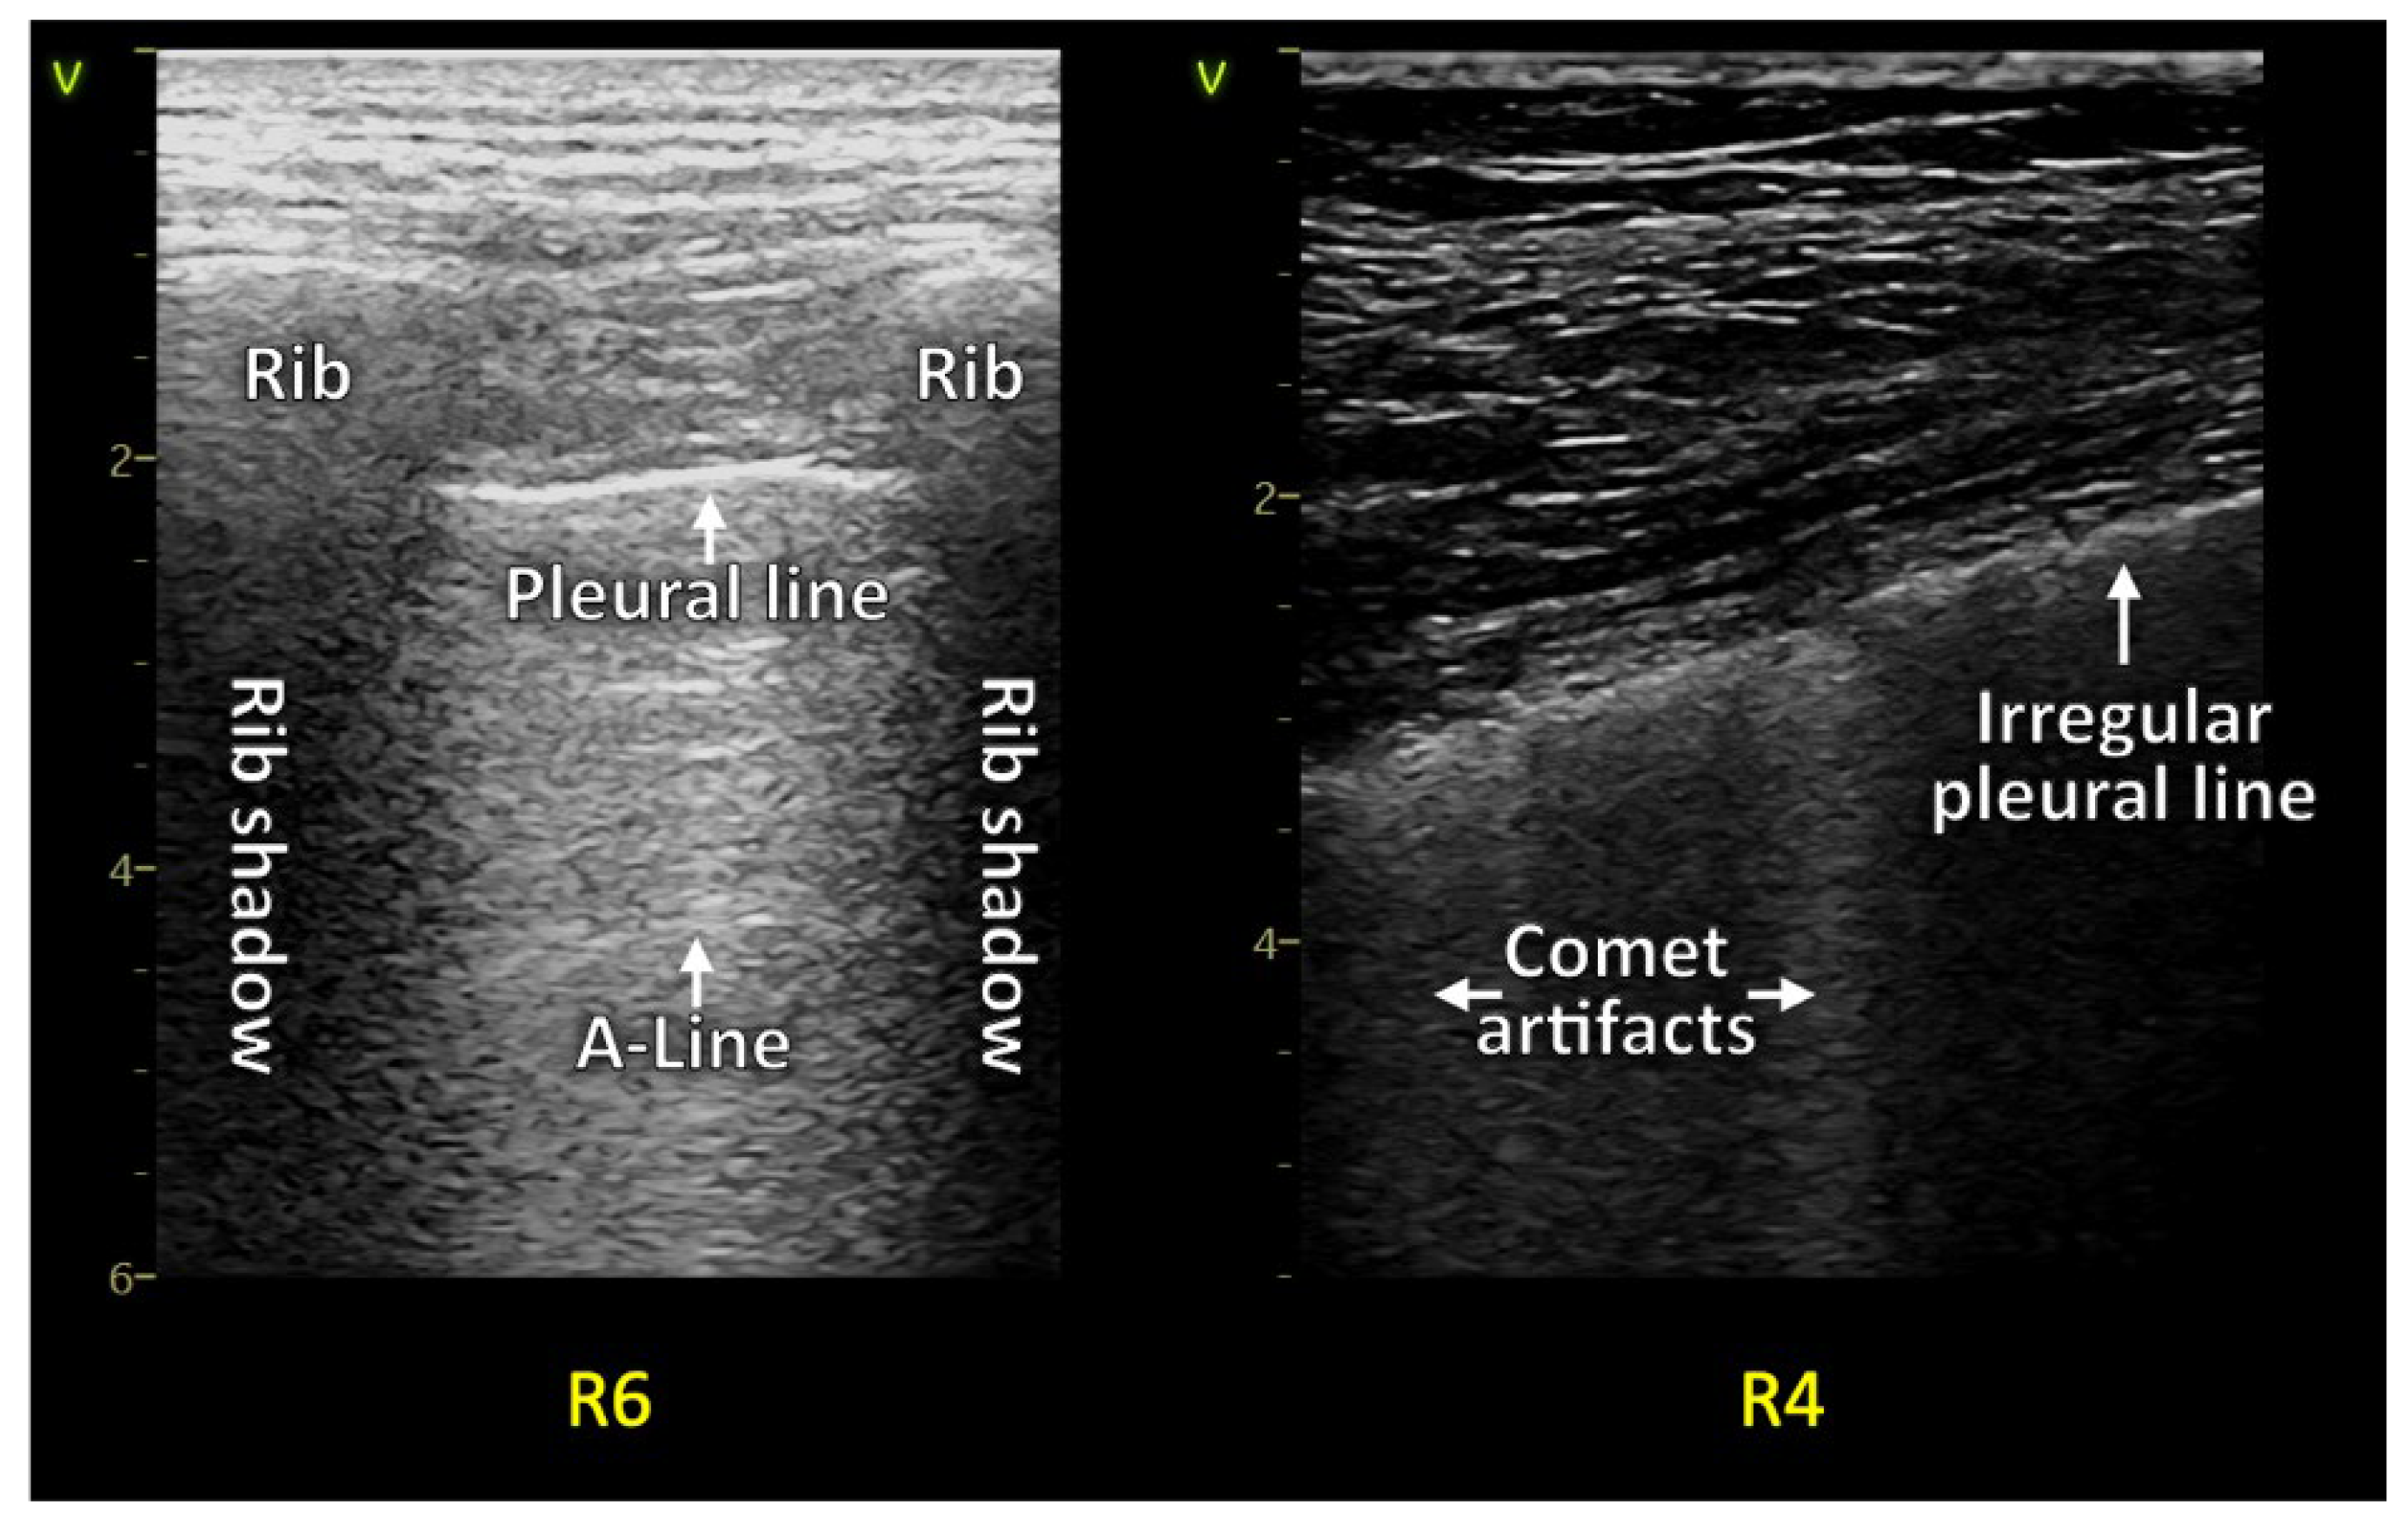

1.1. Background Lung Ultrasound

1.1.1. Reverberation Artifacts

1.1.2. Consolidations and Pleural Effusion